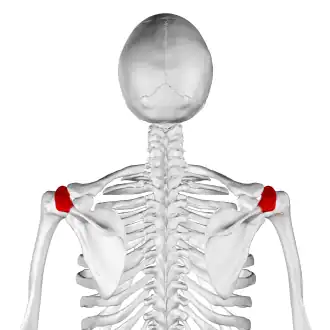

![]() Skeleton, posterior view. Acromion of each scapula shown in red. | |

In human anatomy, the acromion (from Greek: akros, "highest", ōmos, "shoulder", pl.: acromia) or summit of the shoulder is a bony process on the scapula (shoulder blade). Together with the coracoid process, it extends laterally over the shoulder joint. The acromion is a continuation of the scapular spine, and hooks over anteriorly. It articulates with the clavicle (collar bone) to form the acromioclavicular joint.[1]

Structure

The acromion forms the summit of the shoulder and is a large, somewhat triangular or oblong process, flattened from behind forward. It projects laterally at first, then curves forward and upward to overhang the glenoid fossa.[2] It starts from the base of acromion which marks its projecting point emerging from the spine of scapula.[3]